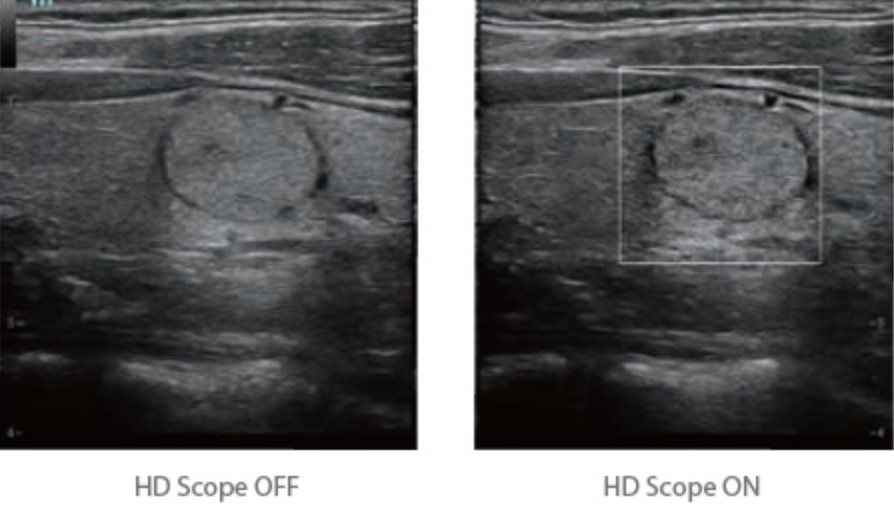

HD Scope: By processing channel data retrospectively, HD Scope enables tissue-specific enhancement with improved detailed information and image contrast on specific region of interest.